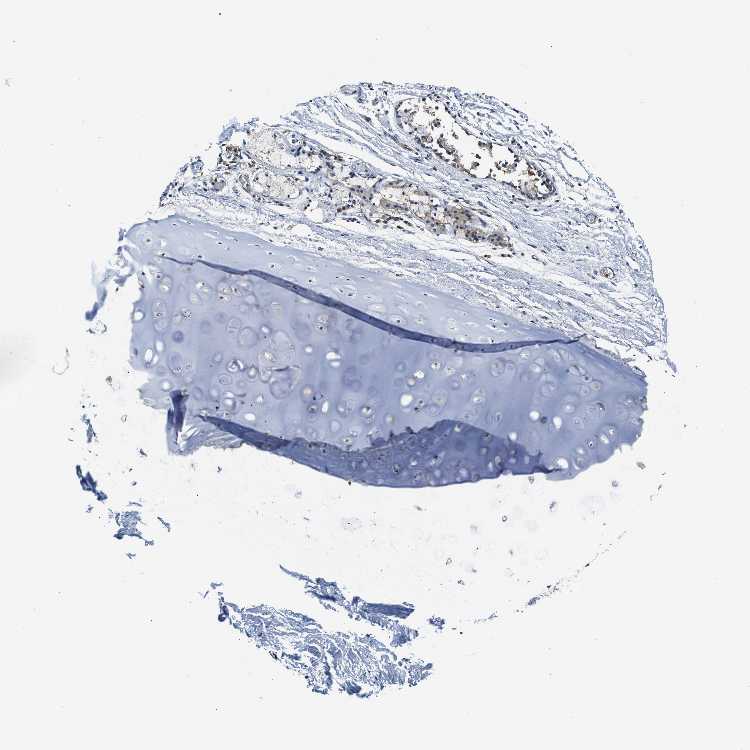

TISSUE PRIMARY DATA SOFT TISSUE Show tissue menu

SOFT TISSUE - Expression summary

SOFT TISSUE 1 - Antibody stainingi

Antibody staining in the annotated cell types in the current human tissue is reported as not detected, low, medium, or high, based on conventional immunohistochemistry profiling in selected tissues. This score is based on the combination of the staining intensity and fraction of stained cells.

Each image is clickable and will lead to virtual microscopy that enables deeper exploration of all samples and also displays staining intensity scores, fraction scores and subcellular localization as well as patient and tissue information for each sample.

Antibody HPA018908Antibody CAB004034

Chondrocytes Not detected-

Fibroblasts Not detectedMedium

Peripheral nerve Not detectedMedium

SOFT TISSUE 2 - Antibody stainingi

Peripheral nerve LowMedium